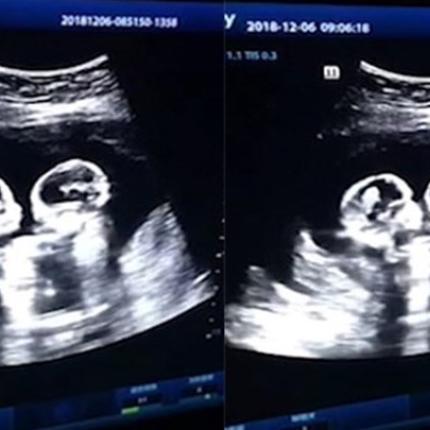

ΟΜΟΖΥΓΩΤΙΚΑ ΔΙΔΥΜΑ